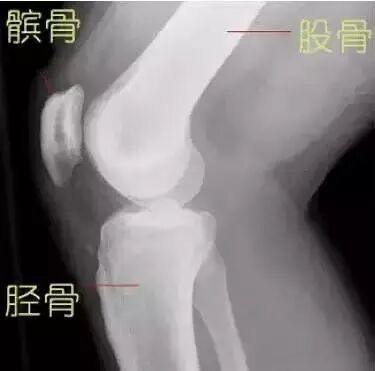

膝关节作为人体最大最复杂的关节,由股骨下端、胫骨上端和髌骨共同构成。其中胫骨上端基本上是一个平面,而股骨下端的关节面则是一个椭圆形,两个关节面一圆一平,并不完全贴和,所以需要半月板来帮助关节面完整贴和。